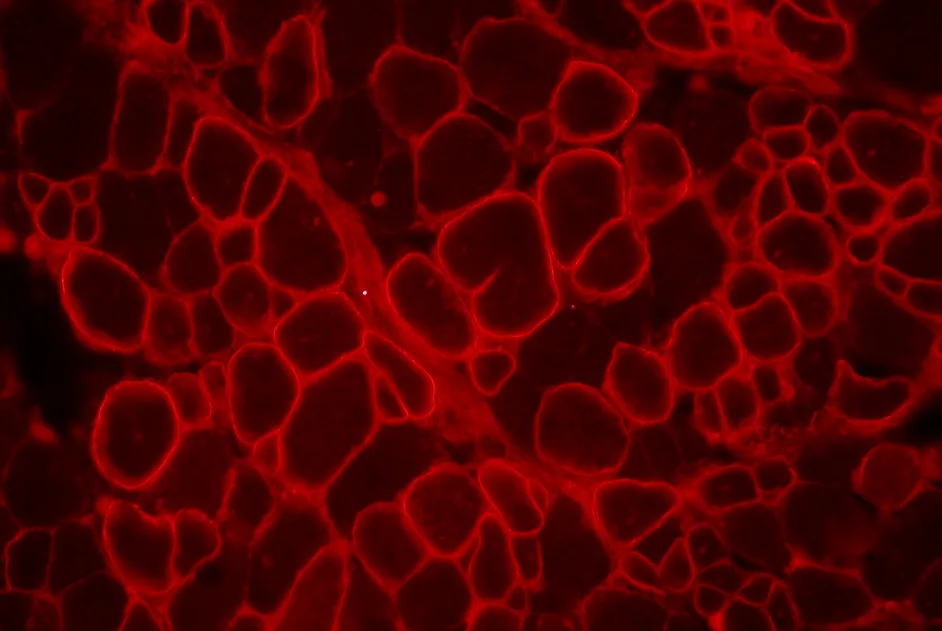

L’expression de dysferline est partiellement restaurée par transplantation de mésangioblastes de souris dans un modèle murin de dysferlinopathie.